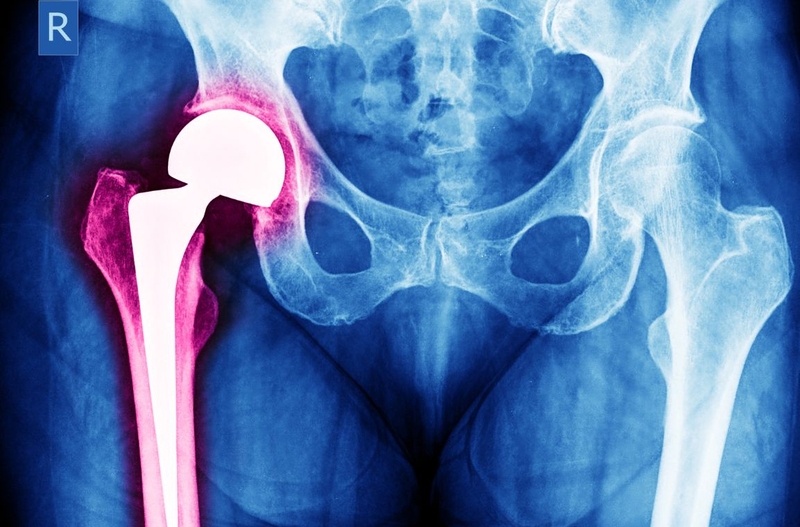

Hình ảnh chụp X quang khớp là căn cứ để bác sĩ đánh giá, chẩn đoán bệnh về khớp. Đây cũng là cơ sở để bác sĩ xác định phương pháp điều trị bệnh về khớp như điều trị nội khoa, điều trị ngoại khoa hoặc phẫu thuật thay khớp. Bác sĩ sẽ chỉ định chụp X quang khớp trong các trường hợp bệnh nhân bị đau đớn, khó chịu dai dẳng ở khớp mà không rõ nguyên nhân. Khảo sát hình ảnh có thể phát hiện các bất thường ở khớp vai, khớp cổ tay, khớp háng, khớp gối, khớp cổ chân.